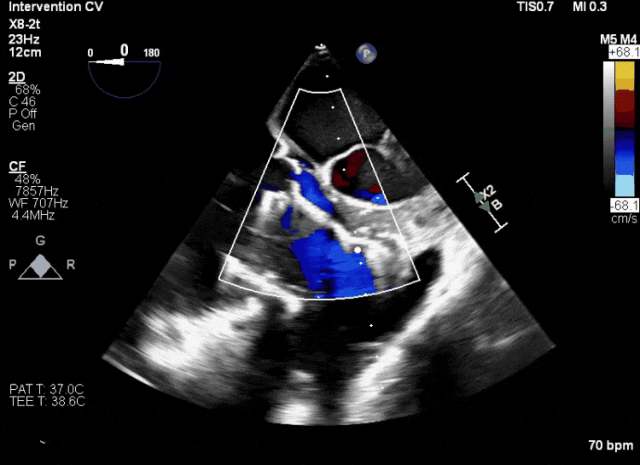

術(shù)前超聲顯示三尖瓣重度反流合并拴系

術(shù)中TEE成像困難,偽影干擾

術(shù)后DSA、超聲顯示人工瓣膜穩(wěn)定性良好,瓣葉啟閉正常,無瓣周漏